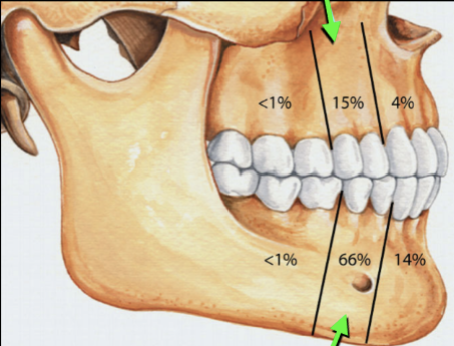

Describe the radiographic features of this Buccal Bifurcation Cyst?

Buccal Bifurcation of Molars

Roots Displaced Lingually

Occlusal Plane Inclined Buccally

Lingual Cusp Higher on BWs and PAs